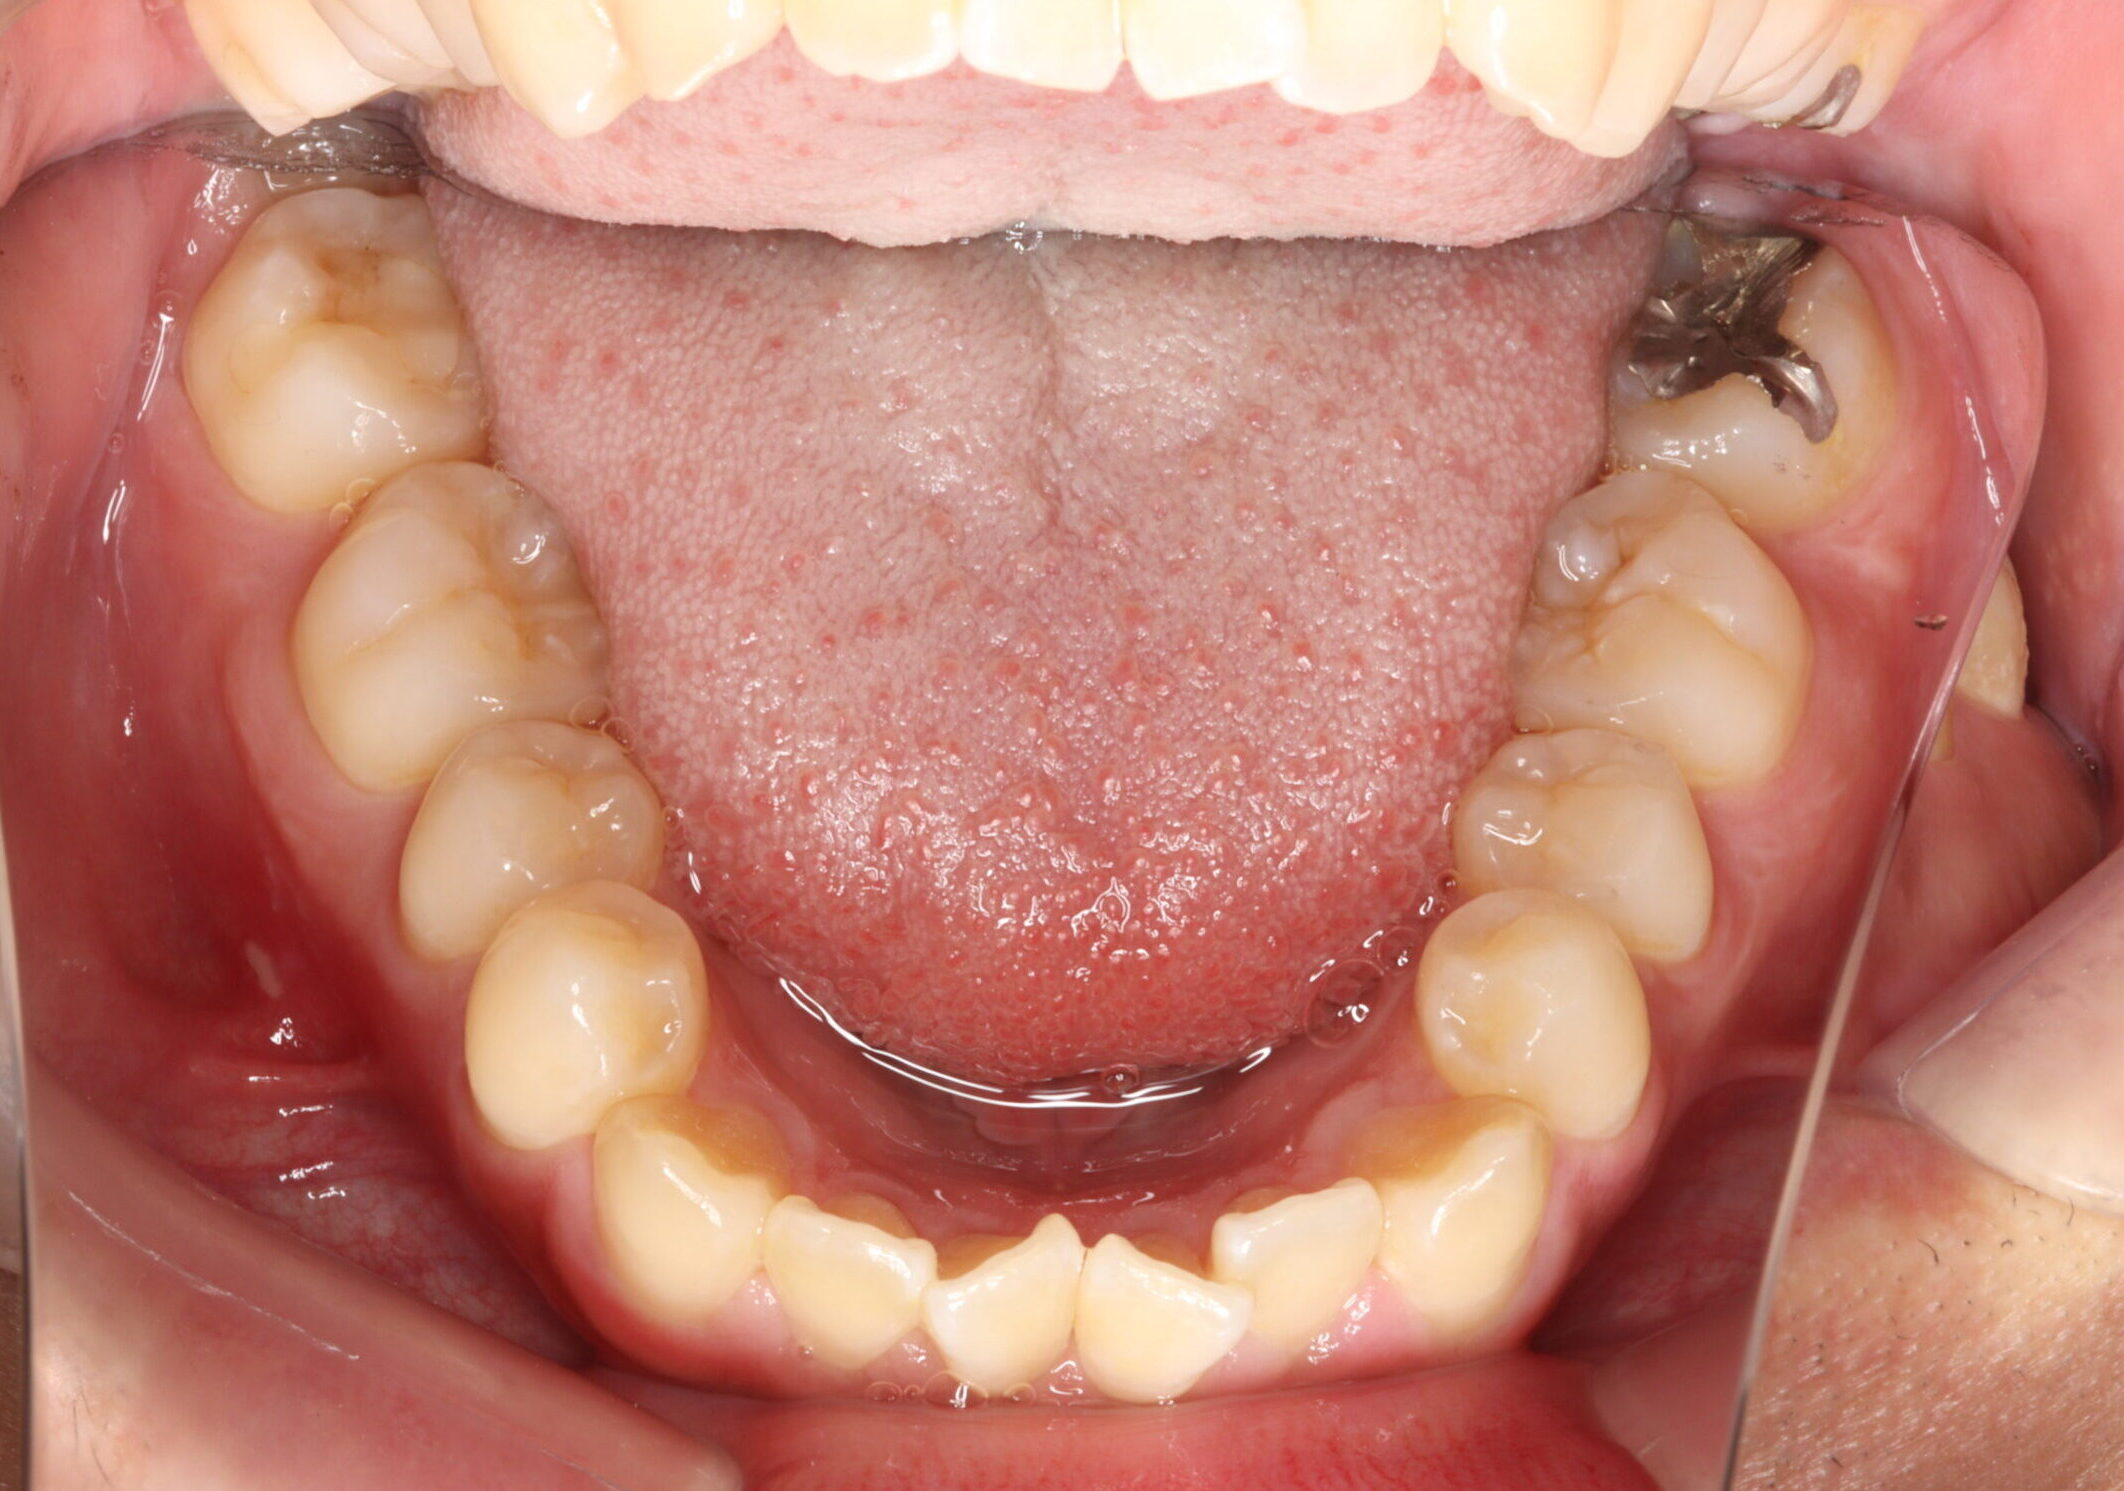

治療前

【診断】開咬、叢生(でこぼこ)、上下顎前歯唇側傾斜、舌突出癖

【治療方法】マルチブラケット装置にて排列を行う。咬合の確立のため顎間ゴムを併用し、舌突出癖の改善のため筋機能療法を行う